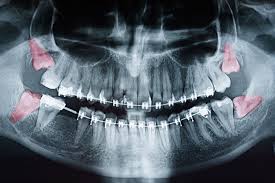

The Problem with Wisdom Teeth Today

For most modern people, wisdom teeth cause problems rather than solve them.

Because the human jaw has shrunk over evolutionary time, there is often not enough room for the third molars to erupt in a healthy, functional position.

When they cannot erupt correctly, the following problems develop:

Impaction — The tooth gets stuck beneath the gum or jawbone, unable to fully emerge.

Crowding — The erupting molar pushes against neighboring teeth, shifting them out of alignment.

Infection (Pericoronitis) — A flap of gum tissue over a partially erupted tooth traps bacteria and food. This causes painful inflammation and infection.

Cyst Formation — In rare cases, the sac around the developing tooth fills with fluid. These cysts can expand and damage surrounding jawbone and nerves.

Decay — Because wisdom teeth sit so far back, they are difficult to brush and floss properly, making them prone to cavities.

Damage to Second Molars — A poorly angled wisdom tooth can press against the root of the adjacent second molar, causing decay or resorption.

Wisdom Teeth Impaction by the Numbers

Impaction is far more common than most people realize.

According to the American Association of Oral and Maxillofacial Surgeons, approximately 90% of people have at least one impacted wisdom tooth by age 25.

About 37% of individuals globally have at least one clinically impacted wisdom tooth. Research shows that roughly 85% of impacted wisdom teeth are positioned in one of these angulations: horizontal, vertical, or mesioangular.

Mesioangular impaction, where the tooth tilts toward the front of the mouth, accounts for approximately 44% of all impaction cases.